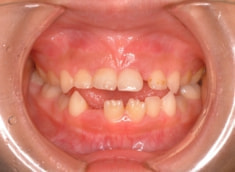

治療前

治療開始時